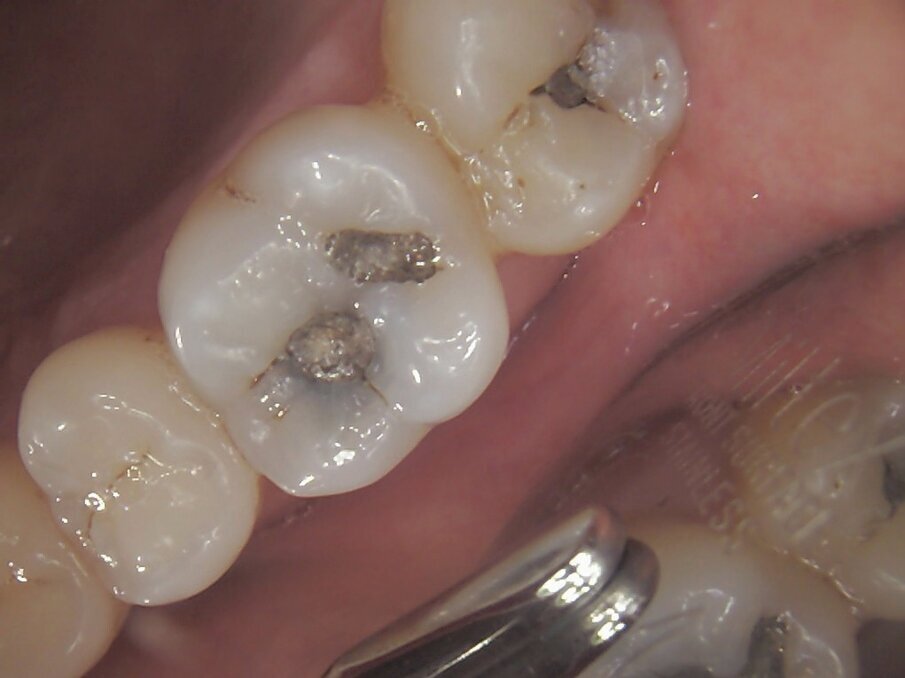

The amalgam restorations were removed with high volume suction, Swedish clean up suction tips, maximum water flow with High speed hand piece. Appropriate supplements were given to the patients to assist in detoxification and flushing the body of any amalgam particulate which entered the throat and gut. The carious and stained dentine, and fractured weakened enamel was removed with slow speed and maximum water flow.

The patient was called the following day and reported complete satisfaction with aesthetics, no afterpain and said her "bite feels normal". (Fig. 11)